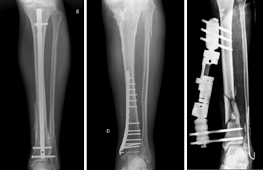

Questo tipo di fratture che, quindi, necessitano di una fissazione chirurgica verranno rese stabili da mezzi di sintesi diversi; si parla in questo caso di osteosintesi.

Durante l’intervento di osteosintesi i frammenti ossei vengono riallineati con appositi strumentari e vengono fissati con fili metallici, viti, placche, chiodi, fissatori esterni, ecc.

Ognuno di essi presenta specifiche peculiarità che ne determinano vantaggi e svantaggi. La scelta del mezzo di sintesi viene fatta dal Chirurgo in base a molteplici considerazioni (tipo di frattura, condizioni del paziente, qualità dell’osso). La maggior parte dei mezzi di sintesi è costituita da leghe metalliche, generalmente il titanio, che sono perfettamente biocompatibili. Essi possono, pertanto, rimanere in situ senza creare particolari problemi. Nei pazienti giovani o nel caso in cui i mezzi di sintesi diano fastidio perché troppo superficiali o perché determinano limitazione del movimento, si tende a rimuoverli dopo un tempo adeguato dalla guarigione (in genere dopo circa 18-24 mesi dalla frattura).

Nuovi strumentari e tecniche chirurgiche permettono l’osteosintesi mininvasiva che ha il grande vantaggio di limitare al massimo l’esposizione chirurgica e quindi accelerare la ripresa funzionale.

Pseudoartrosi

Quando una frattura non guarisce si parla di pseudoartrosi. Si definisce così perché la frattura, non guarendo, rende mobile (a volte senza dolore) il segmento formando una nuova articolazione. Le pseudoartrosi possono essere atrofiche, con scarse potenzialità biologiche, o ipertrofiche in cui la sola stabilizzazione del sito di frattura porta a guarigione l’osso.

Condizioni patologiche o stili di vita che aumentano il rischio di pseudoartrosi sono costituite dal fumo di sigaretta, dal diabete, da infezioni o gravi traumi che determinano la necrosi dei tessuti molli adiacenti all’osso (muscoli, fasce, tendini). Il trattamento di una pseudoartrosi prevede interventi complessi, utilizzando tecnologie avanzate sia per quanto riguarda gli strumentari e i presidi chirurgici sia nel campo della bioingegneria e della medicina rigenerativa (cellule staminali, biostimolatori/modulatori, ecc.).